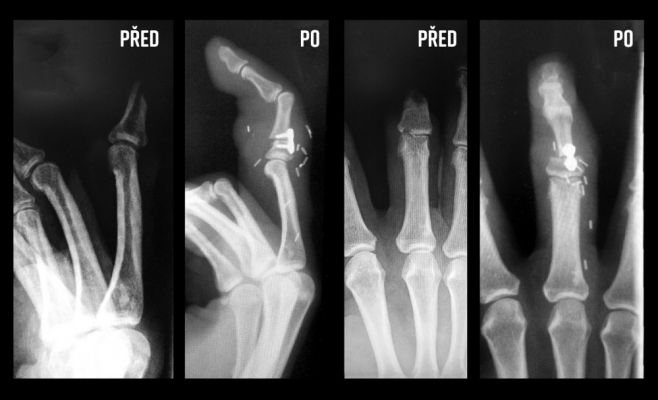

Врачи из Факультетской больницы Оломоуц в середине марта успешно провели уникальную операцию: пересадили палец с ноги на руку. Таким образом, медики спасли рабочую кисть своей коллеги. На 47-летнюю медсестру Хану Колоушкову из Оломоуц напала соседская собака и откусила ей часть среднего пальца на правой руке. Успешный результат операции стал шансом пациентки в будущем вернуться к своей работе.

Трансплантацию пальца провели через четыре дня после происшествия. До этого медики сделали все необходимые процедуры, чтобы исключить возможность заражения после укуса собаки. Операция длилась 11 часов. Как пояснил Богумил Залешак, сначала необходимо было подготовить кровеносный сосуд, затем удалить палец на ноге и подготовить руку к пересадке. Только такая последовательность позволила добиться успешного результата.

Сегодня пациентка находится дома, но под строгим наблюдением медиков. После операции в течение 14 дней хирурги боролись за «жизнь» пальца. «Нам неоднократно приходилось чистить кровеносные сосуды или заменять их части новыми трансплантатами. Но в конечном итоге всё получилось. Функция руки может восстановиться до девяноста процентов, и если сенсорные нервы заживут хорошо, мы сможем в ближайшее время добиться очень хорошей чувствительности пальца», - подтвердил главврач. Сама Хана Колоушкова полагает, что сможет вернуться на работу в больницу уже в начале июня.